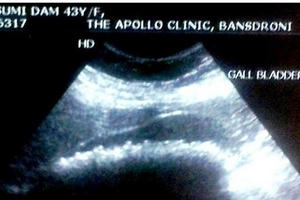

Để gần 400 viên sỏi được lấy ra từ túi mật bệnh nhân vào bát đựng bệnh phẩm, các bác sĩ cũng sốc vì số sỏi được lấy ra không khác gì một mẻ ngô rang, với đường kính lớn nhất là 1cm.